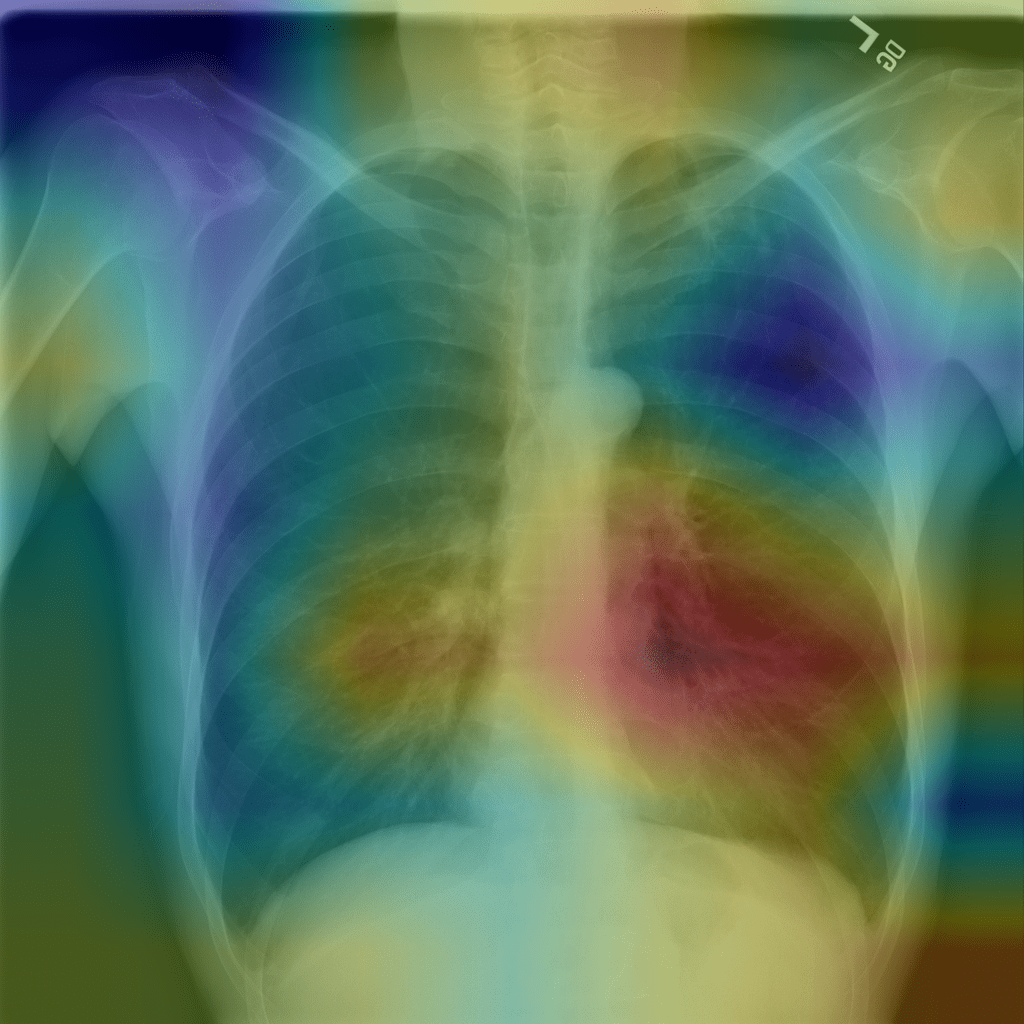

CheXNet (Stanford, 2017)

- An ML system trained on 112K labeled chest X-rays

- Detects pneumonia at radiologist-level accuracy

- Heatmap shows where the model "looks"